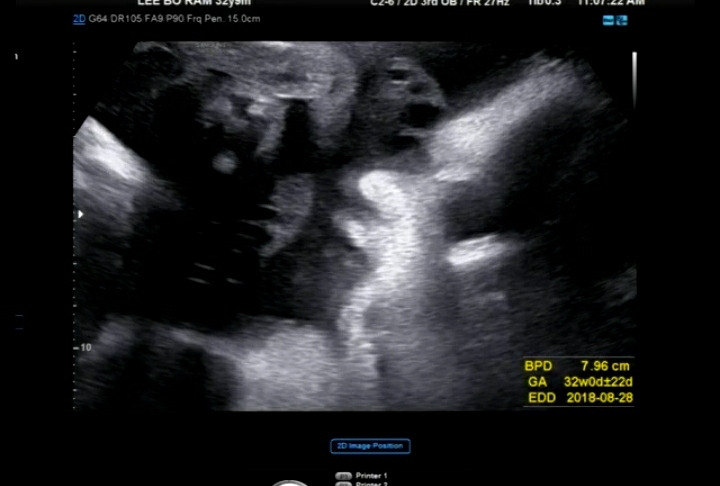

뱃속에서 보여준 옆모습